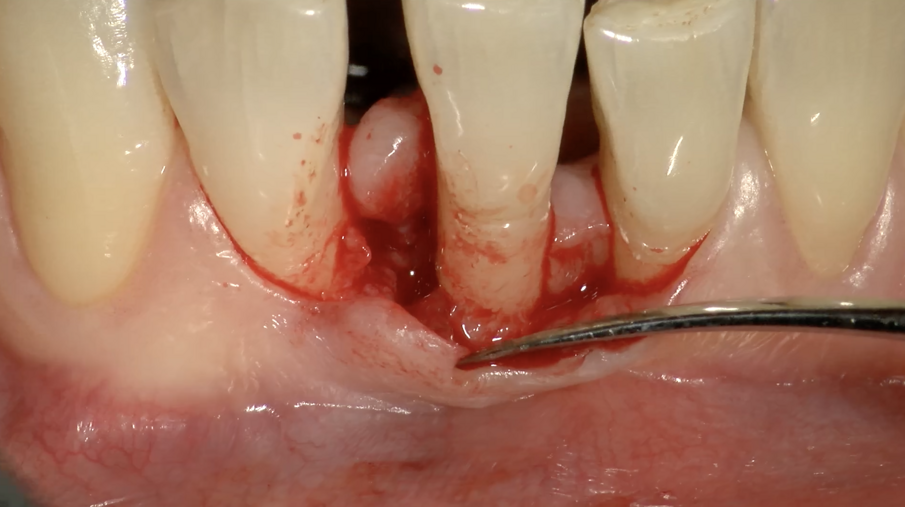

Il Paziente veniva premedicato con Zitromax 500 mg e Ibuprofene 400 mg. Eseguita anestesia loco regionale con articaina 1:100.000 con adrenalina veniva sollevato un lembo muco periosteo a spessore totale con tecnica di preservazione di papilla MPPT (Cortellin i 1995) e incisione intrasulculare (Figg 6d, 6e). Il difetto in sede interprossimale e vestibolare è stato degranulato con ultrasuoni e curette manuale. Raggiunta la perfetta decontaminazione del sito è stata preparata la barriera GUIDOR matrix barrier partendo dalla configurazione specifica per difetti interprossimali (DC double curved) in modo da renderne corretta la dimensione mesio distale e apico coronale (Fig. 6f) .

Fig. 6e - Difetto infraosseo mesiale.

Fig. 6f - Membraba Guidor in situ.